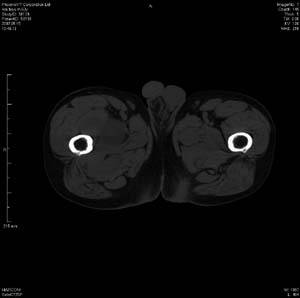

男 63岁 右大腿无痛性肿块11年,x片右大腿软组织肿块影,余无明显异常.ct值-13__239hu

右大腿股内侧股与收肌间隙间多发囊实性占位,界清.内示斑点状钙化.局部骨质无异常.肌肉推压移位表现.

考虑肌间隙病变.可有1,神经来源肿瘤.2,血管来源病变.3,淋巴来源肿瘤.4,脂肪来源肿瘤.5,滑膜来源肿瘤.结合病史只能考虑良性占位.建议增强或mri进一步分析.

同意,病史较长,病变周围分界清晰,考虑良性病变。病灶内有多发斑点状钙化,沿肌间隙生长,血管瘤或淋巴管瘤首先考虑。